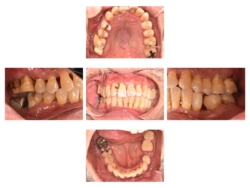

歯間ブラシが全て!歯周病治療症例①

歯間ブラシは歯周病治療に必須です。 歯周病は歯間から始まります。 フロスは?と思われるかもしれませんが、フロスは虫歯予防に使用するものです。 EFP(ヨーロッパ歯周病連盟)のガイドラインでも、歯間ブラシが第一選択になっています。